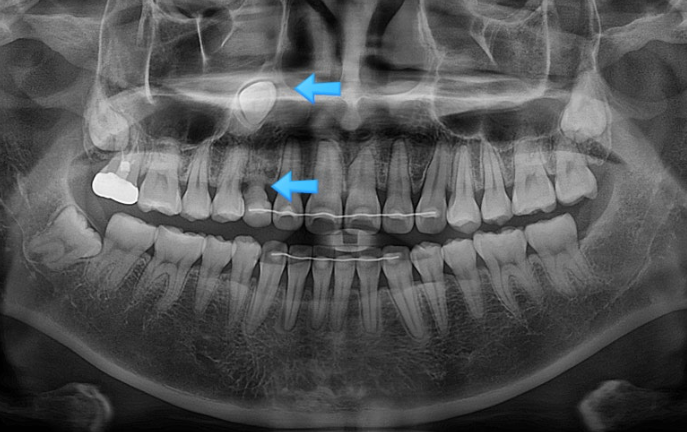

아래 앞니 뿐만 아니라 파란화살표 앞니도 뿌리가 앞으로 나가있습니다. 아직 아래앞니처럼 잇몸퇴축이 일어나지는 않았지만, 튀어나간 뿌리를 입천장쪽으로 데려오는 치료를 해야 잇몸이 내려가는걸 예방할 수 있습니다.

24.10